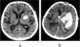

Cerebral edema is excess accumulation of fluid (edema) in the intracellular or extracellular spaces of the brain. This typically causes impaired nerve function, increased pressure within the skull, and can eventually lead to direct compression of brain tissue and blood vessels. [Source: Wikipedia ]